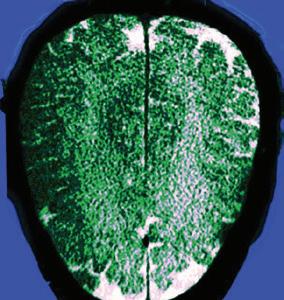

University of Freiburg, Germany

• Dr. Deepak Venkateshvaran

University of Cambridge, United Kingdom

• Stanislas Rohart

CNRS/Université Paris-Saclay, France

• Dr. Tobias Cramer